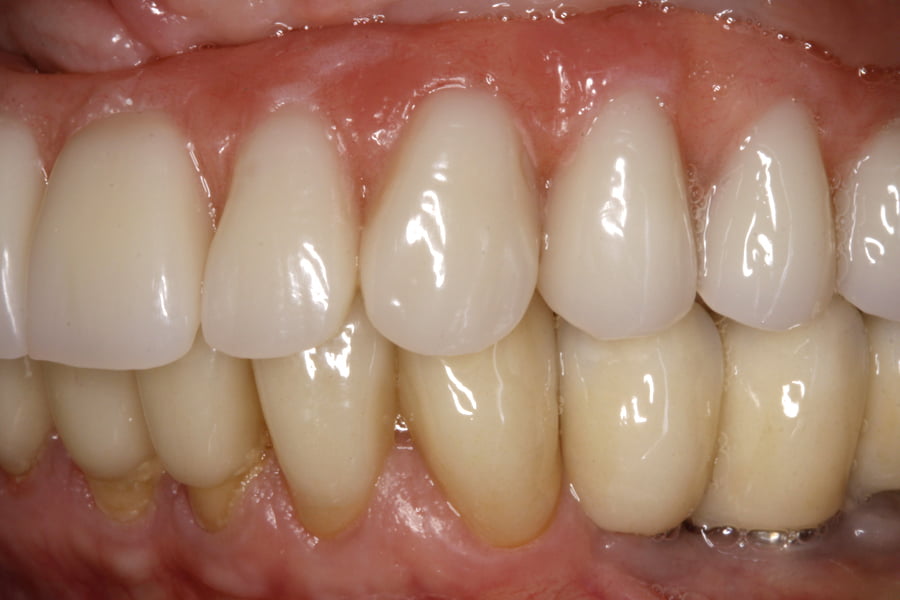

As seguintes imagens apresentam um dos casos incluídos no estudo (figura 03 – 15).